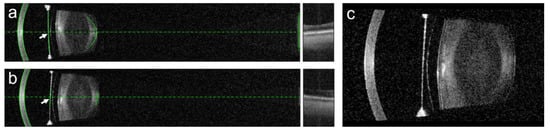

- Baumeister, M.; Bühren, J.; Kohnen, T. Position of angle-supported, iris-fixated, and ciliary sulcus-implanted myopic phakic intraocular lenses evaluated by Scheimpflug photography. Am. J. Ophthalmol. 2004, 138, 723–731. [Google Scholar] [CrossRef]

- Rabsilber, T.M.; Khoramnia, R.; Auffarth, G.U. Anterior chamber measurements using Pentacam rotating Scheimpflug camera. J. Cataract. Refract. Surg. 2006, 32, 456–459. [Google Scholar] [CrossRef] [PubMed]

- Baïkoff, G. Anterior segment OCT and phakic intraocular lenses: A perspective. J. Cataract. Refract. Surg. 2006, 32, 1827–1835. [Google Scholar] [CrossRef]

- Gaurisankar, Z.S.; van Rijn, G.A.; Luyten, G.P.M.; Beenakker, J.M. Differences between Scheimpflug and optical coherence tomography in determining safety distances in eyes with an iris-fixating phakic intraocular lens. Graefes. Arch. Clin. Exp. Ophthalmol. 2021, 259, 231–238. [Google Scholar] [CrossRef]